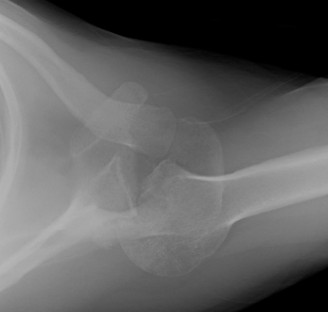

Imaging should include x-rays, which may demonstrate posterior glenoid bone loss or an impaction fracture on the anterior-superior humeral head (Fig. 2–38). CT images with 3D reconstructions can be very useful when assessing the extent of glenoid bone loss and evaluating glenoid and humeral version. Normal glenoid version is from −2 to −8 degrees of retroversion, and this may be increased in posterior instability. MRI can also be useful when assessing the posterior labrum (Fig. 2–39).

Figure 2–38 Radiographs showing a posterior shoulder dislocation.

Figure 2–39 MRI showing a posterior labrum tear.